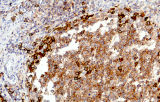

- Assegnazione del lignaggio & principali diagnosi differenziali: Fenotipizzazione cellule B vs cellule T (es. CD20 vs CD3), supportata da fattori di trascrizione nucleari delle cellule B come PAX5 quando i marcatori pan-B sono deboli/assenti.

- LLC/LLS: co-espressione caratteristica di CD5 e CD23 nelle cellule B CD20+ (l'interpretazione richiede consapevolezza del pattern perché sono presenti cellule T reattive).